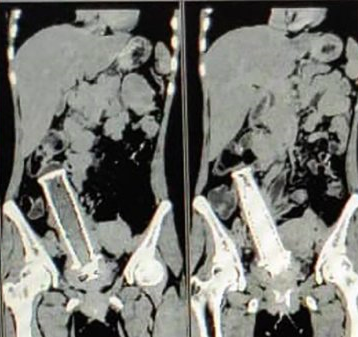

Một người phụ nữ 30 tuổi cảm thấy bị đau bụng dữ dội khiến được đưa đi cấp cứu tại Bệnh viên, khiến các bác sĩ đã quét cơ thể cô bằng CT và kinh hoàng phát hiện ra có một vật thể lạ tương đối lớn nằm trong tử cung của người phụ nữ này, đã làm cho 19 bác sĩ đã thay phiên nhau lấy dị vật trong ca phẫu thuật kéo dài 4 giờ đồng hồ..

Theo Mstar, người phụ nữ 30 tuổi này đã được đưa đi cấp cứu tại Bệnh viên MY sau khi cảm thấy bị đau bụng dữ dội.

Các bác sĩ đã quét cơ thể cô bằng CT và kinh hoàng phát hiện ra có một vật thể lạ tương đối lớn nằm trong tử cung của cô.

Trải qua thêm vài lần quét nữa, vật thể bí ẩn đó được xác định là một tay cầm xe máy.

Người phụ nữ này ngay lập tức được đưa vào phòng mổ, 19 bác sĩ đã thay phiên nhau lấy dị vật trong ca phẫu thuật kéo dài 4 giờ đồng hồ.